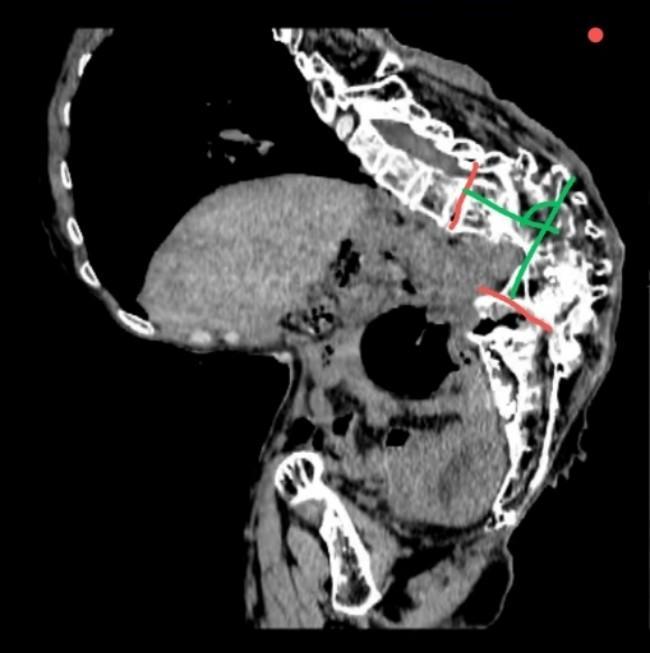

患者因“絕經后陰道流血10天,診刮病理提示子宮內膜樣腺癌”入院。該患者其幼年曾患結核,導致嚴重脊柱后凸側彎(俗稱“羅鍋”),無法平臥,手術時僅能耐受接近坐位的特殊體位,這導致手術操作空間嚴重受限、暴露困難,術中極易損傷脊柱脊髓,術后拔管困難與低氧血癥風險高,加之患者先天性聾啞,醫患溝通存在障礙,手術難度與風險極高。

針對患者的復雜病情,在婦科副主任兼奧體院區婦科主任劉鳴的指導下,副主任醫師耿鋒帶領團隊聯合麻醉與圍術期醫學科、重癥醫學科進行了多學科協作攻關,制定了詳盡的手術方案,就手術體位、手術路徑、切口選擇、手術范圍、術中突發狀況應急處理以及術后生命體征監測等環節均進行了充分討論與周密準備。子宮內膜癌的標準術式是筋膜外全子宮切除術+雙側附件切除術+前哨淋巴結活檢/系統性淋巴結清掃,鑒于該例患者手術體位擺放極其困難及盆腹腔內操作空間極為有限,團隊最終決定實施經腹子宮次全切術。手術由耿鋒副主任醫師主刀,主治醫師張碩、住院醫師曹燁擔任助手。在麻醉與圍術期醫學科副主任徐艷冰、副主任醫師楊淼、住院醫師晁慧玲的精準評估與麻醉下,巡回護士徐雯、許彩燕、李英英、李倩對手術體位恰當擺放,器械護士崔瑞言密切配合,手術團隊憑借豐富的臨床經驗和精湛的操作技巧,在極有限的空間內順利完成子宮次全切術?;颊咝g后轉入重癥醫學科,在重癥醫學科副主任醫師王啟志等醫護人員的嚴密監護下,患者順利拔除氣管插管,術后第1天轉回婦科病房。通過給予擴張支氣管、化痰等措施,患者克服了低氧血癥,術后恢復良好,已順利出院。